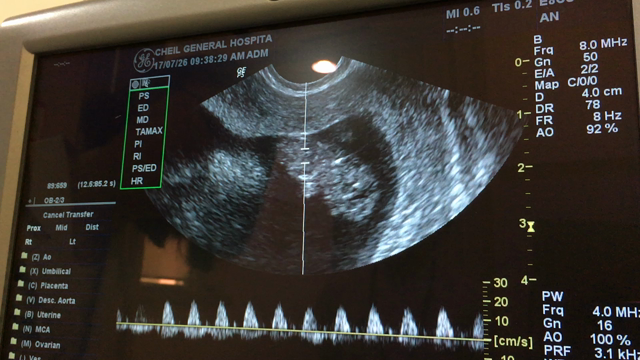

1回目の血液検査とエコー検査

出張後の検診~9w5d~

出産予定日確定